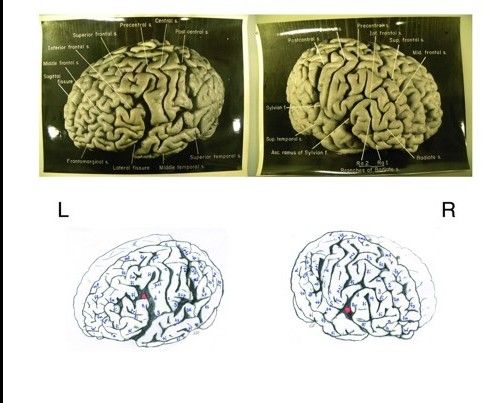

近期对14张新发现的爱因斯坦大脑切片进行的研究显示,这位大科学家的大脑的确在很多方面是与众不同的。这些大脑切片是当初在爱因斯坦去世之后被保留下来用作研究之用的。不过,科学家们目前仍然不清楚爱因斯坦大脑中所显示的那些额外的褶皱和沟回究竟是如何转化为爱因斯坦惊人的思维能力的。

哈维对大脑进行了拍摄,将其切成240份并置于一种树脂般的物质之中。随后他进一步将这份大脑样品切成多达2000片薄片用于显微镜研究。在接下来的年代里,他将这些切片分发给了至少18位全球各地的研究者。但是所有这些切片中唯独缺失哈维自己保留的那些样本切片,没有人知道这些切片现在究竟在什么地方。随着这些研究人员相继退休或逝世,很多样本或许已经遗失了。

然而,福柯的研究工作仅仅建立在哈维给出的一小部分切片照片的基础之上,后者于2007年离世。2010年,哈维的继承人同意将他们所收藏的所有相关材料移交给美国陆军国家健康和医学博物馆。

在本月16日发表于《大脑》杂志上的一篇文章中,福柯和新泽西州罗伯特-伍德·约翰逊医学院的神经学家弗里德里克·莱玻尔(Frederick Lepore)以及陆军国家健康和医学博物馆的阿德莱尼·诺尔(Adrianne Noe)相互合作,对此次哈维家族捐赠的14张爱因斯坦全脑图像进行了分析,这些图片之前从未对外展示过。这篇文章中还包括了由哈维家族提供的“路线图”。在这份路线图中记载了爱因斯坦大脑整体与那全部240块部分和各个切片之间的位置对应关系。当初哈维制作这一路线图正是寄希望于方便后来的科学家们继续开展相关的研究工作。